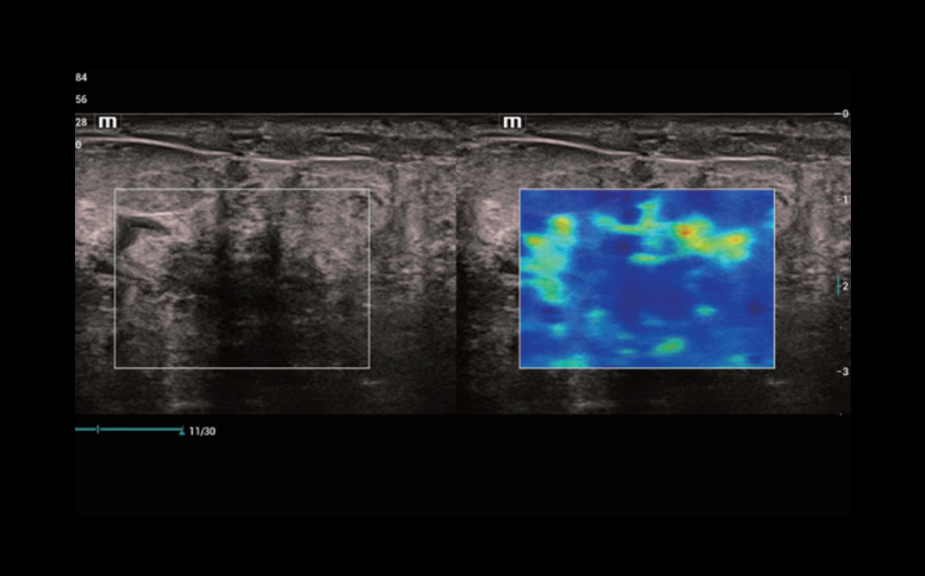

Focal Lesion Diagnosis with Perfusion: UWN+ Contrast Imaging

Utilization of both the 2nd harmonic and non-linear fundamental signals

Greater sensitivity for minor signals and longer agent duration with lower MI

CEUS of metastatic liver cancer